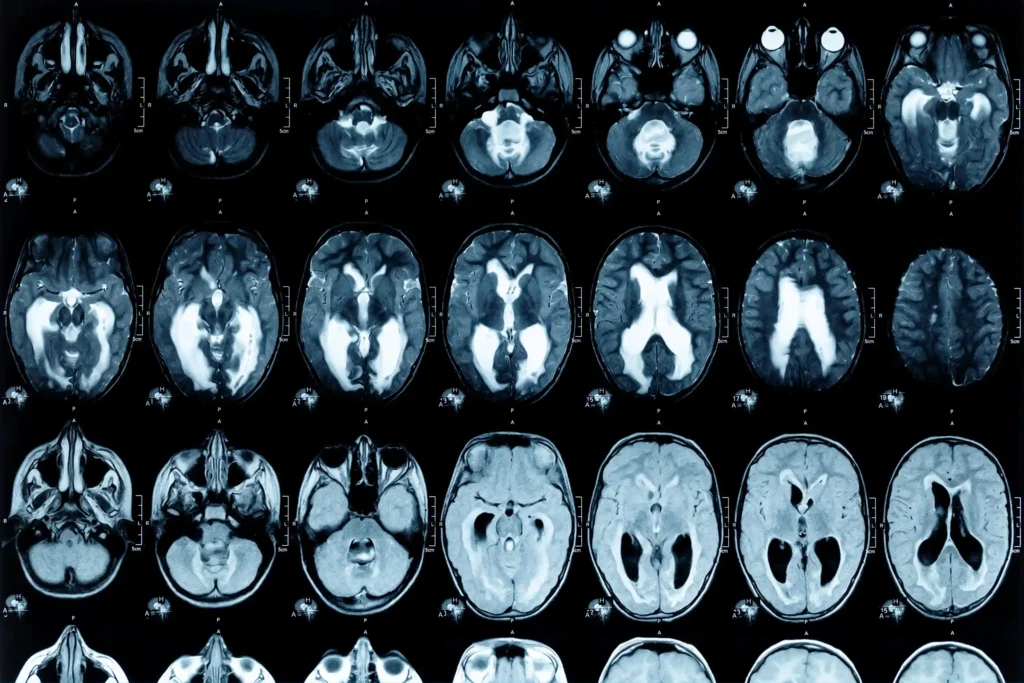

The purpose of an MRI scan is to create incredibly detailed images of organs, soft tissues, bone, and virtually all other internal body structures. Unlike X-rays, which use radiation, MRIs use powerful magnetic fields and radio waves. This makes them exceptionally safe and incredibly useful for spotting even the tiniest anomalies. Doctors use them to diagnose a vast range of conditions, from torn ligaments and herniated discs to brain tumors and multiple sclerosis. It's like having a microscopic magnifying glass for your internal organs, offering insights that other imaging techniques simply can't provide. The benefits are enormous, offering a clearer path to diagnosis and, consequently, more effective treatment plans.

Now, about those results. The timeframe for receiving your MRI scan results can vary, and it's not a one-size-fits-all answer. Generally, you can expect them to be ready anywhere from 24 hours to a few days after your scan. This depends on a few factors. Firstly, the complexity of the scan itself. A routine knee MRI might be read faster than a comprehensive brain scan with many sequences. Secondly, the radiologist's workload. These highly trained doctors interpret the images, and their schedules can influence turnaround times. Finally, the urgency of your case plays a role. If your doctor flags your scan as urgent, it will likely be prioritized.